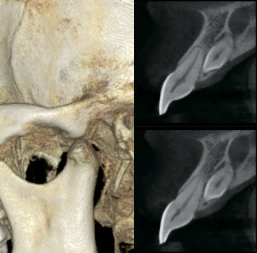

Изображения с высоким разрешением для точной диагностики

Получите исключительную чёткость изображения и настраиваемый объём сканирования с помощью RAYSCAN. Адаптируйте свои снимки в соответствии с вашими конкретными клиническими потребностями, и будьте уверены в том, что запечатлеете каждую сложную деталь и раскроете безграничные возможности.

FOV 10×10 см, 160 μm

FOV 4×5 см, 70 μm

Технология AMF (Адаптивный движущийся фокус) выбирает оптимальный слой изображения для получения чётких панорамных изображений, что позволяет легко определить состояние пародонта пациента и локализацию поражения.